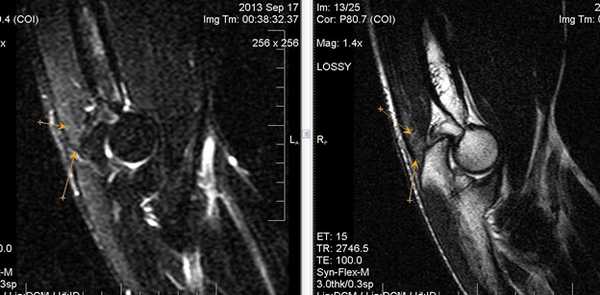

МРТ локтевого сустава в корональной плоскости. В подкожно-жировой клетчатке локтевого сустава отмечаются множественные образования неправильной вытянутой формы, местами сливающиеся между собой — вероятно, венозная мальформация.

МРТ локтевого сустава в сагиттальной плоскости. Отмечается повышенное скопление свободной синовиальной жидкости в полости локтевого сустава. Синовиальная оболочка умеренно гипертрофирована.

б)МРТ локтевого сустава в корональной плоскости. Общее сухожилие разгибателей в месте прикрепления к латеральному надмыщелку плечевой кости неравномерно утолщено, МР-сигнал от него неоднородно повышен на PD FS-ВИ и Т2-ВИ за счет выраженного отека и разволокнения (признаки латерального эпикондилита), общая целость его не нарушена. Окружающие мягкие ткани с признаками отека.